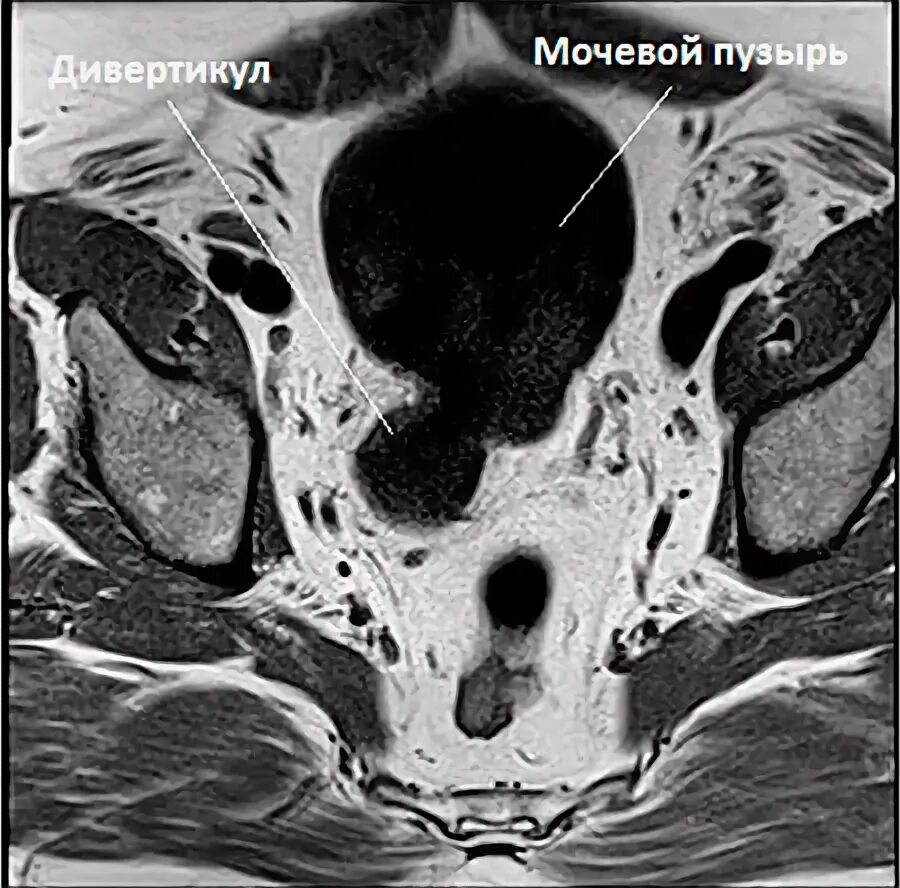

Уплотнение стенки мочевого пузыря